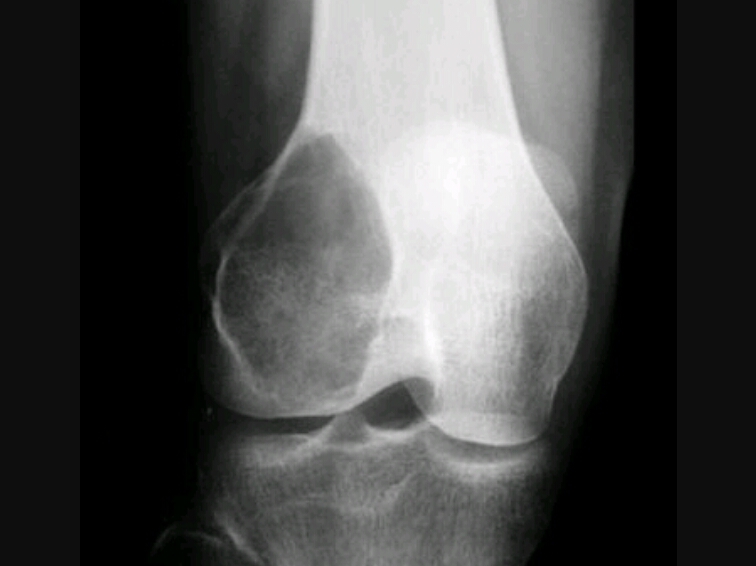

Geographic, eccentric, metaphyseal/epiphyseal, subarticular, soap bubble appearance, lytic, cortical thickening

Giant cell tumor